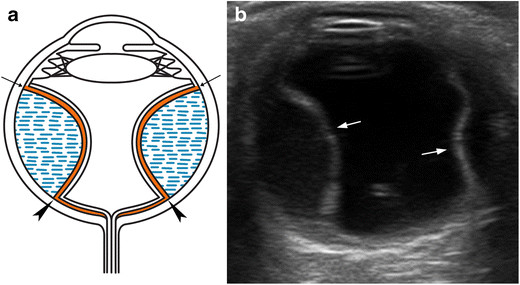

섬유주 절제술은 정상적인 방수의 유출경로인 섬유주가 고장이난 상태에서,

섬유주 일부를 제거하고 절제함으로써,

해당 통로를 통해 눈안쪽(전방, Anterior chamber, AC)에서부터 눈바깥으로 물이 빠져나가도록 통로를 만들어주는 수술입니다.

5. 맥락막 박리 및 전방소실.

수술로 인해서 갑작스럽게 안압이 떨어지면 간혹 맥락막 박리가 발생할수 있습니다.

이는 수술전 안구내의 압력이 높다가, 수술로 인해서 압력이 순간적으로 줄어드니,

눈속의 구조물인 맥락막이, 껍질인 공막에서부터 허탈되어 떨어지는 것을 의미합니다.

이 경우, 안저검나사 B-scan 상에서 Choroidal detachment (맥락막 박리, CD)소견이 관찰됩니다.